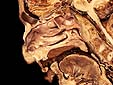

Pared Medial de las Fosas Nasales